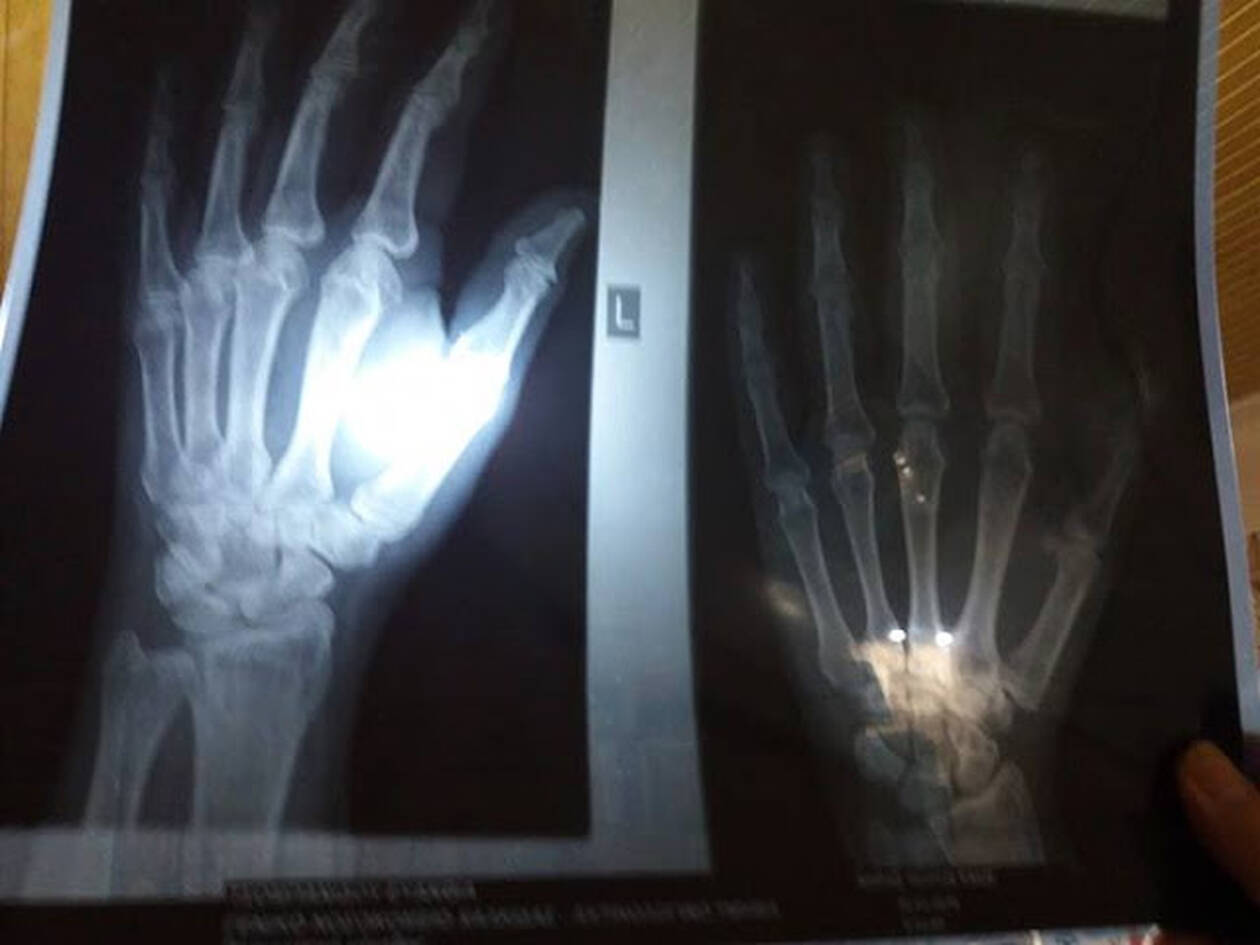

«Η τελική κατάληξη φαίνεται στις φωτογραφίες, με κακώσεις στα γόνατα και ρήξη συνδέσμων στο αριστερό μου χέρι. Λόγω του τραυματισμού μου δε μπορώ να εργαστώ για 10 ημέρες τουλάχιστον. Να χαιρόμαστε την τοπική μας αυτοδιοίκηση. Άντε και εις κατώτερα», συμπληρώνει.